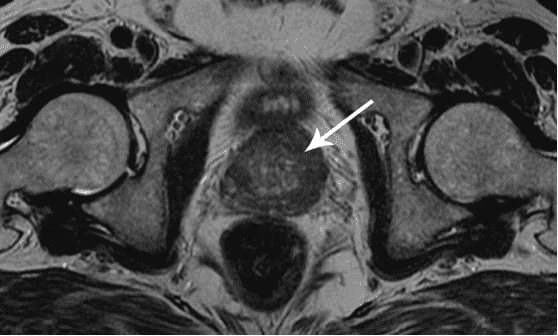

أستطيع أن أرى الرجال الذين يزورونني بسبب التهاب البروستاتا أو تضخم البروستاتا الحميد كل يوم. في الواقع، هذه الأمراض هي حالات ما قبل سرطانية غدة البروستاتا.

كما ترى، ترتبط هذه المشكلات ارتباطًا مباشرًا بممارسة الجنس بانتظام. عندما يتوقف الرجل عن ممارسة الجنس بانتظام، تصاب غدة البروستاتا بالاحتقان، ونتيجة لذلك، يتسبب ذلك في حدوث التهاب ويوقف إنتاج الهرمونات المهمة. بدون علاج طويل الأمد، يتطور التهاب البروستاتا إلى تضخم البروستاتا الحميد الذي يتحول بعد ذلك إلى سرطان.

سرطان البروستاتا ناتج عن عدم ممارسة الجنس لفترة طويلة. توفي رجل 60 سنة.